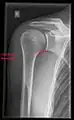

X-ray

Projectional radiography views of the shoulder include:

- Y-projection

The lateral contour of the shoulder should be positioned in front of the film in a way that the longitudinal axis of the scapula continues parallel to the path of the rays. This method reveals:[26]

- The horizontal centralization of the humerus head and socket

- The osseous margins of the coraco-acromial arch and hence the supraspinatus outlet canal

- The shape of the acromion

This projection has a low tolerance for errors and, accordingly, needs proper execution.[26] The Y-projection can be traced back to Wijnblath’s 1933 published cavitas-en-face projection.[27]

CR. shoulay film.

Transaxillary conventional radiography

Y-projection conventional radiography